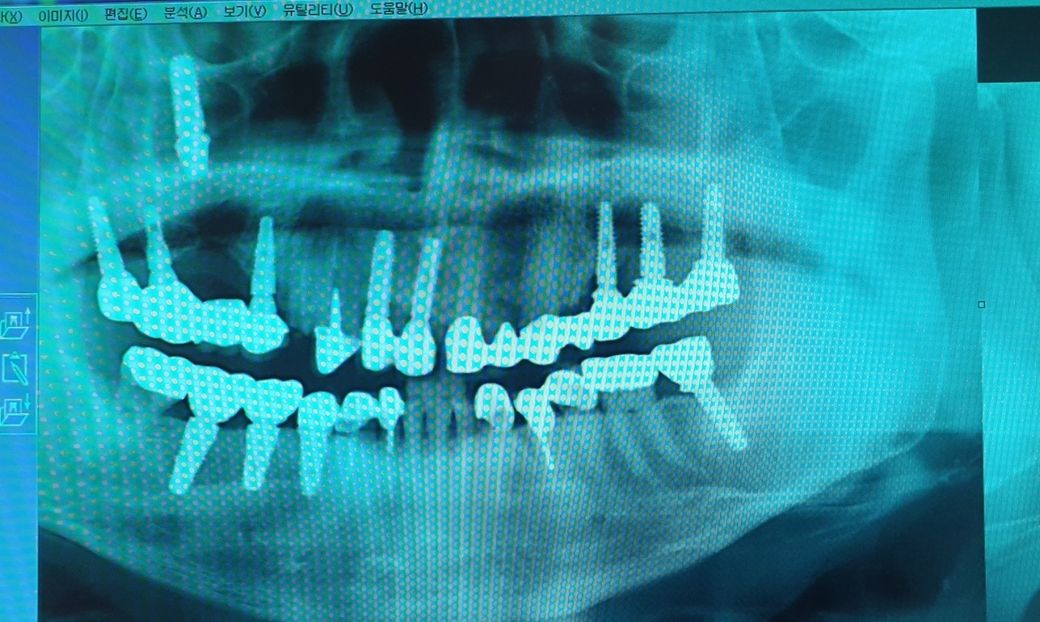

보시다시피 왼쪽 위 어금니쪽의 임플란트 위치가 상당히 치솟아 인터넷에 알아보니 상악동을 뚫고 올라간것으로 보이고,

1. 현재 나타나고 있는 두통 등의 증상이 해당 임플란트가 상악동으로 들어가서 생긴 문제로 보여집니다. 사진 상으로 정확히 보이지 않으나 심각한 상악동염이 동반되고 있는 것으로 보여집니다.

사진으로 봤을 경우 왼쪽위에 보이는 임플란트는 정상적인 위치가 아닌것으로 보이며 사진을 찍을때의 오류가 아니라면 상악동으로 들어갔을 가능성이 있습니다.